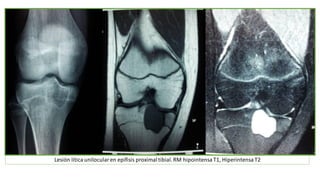

LESION LITICA,

EXPANSIVA Y NO

TRABECULADA

Lesión lítica unilocularen epífisis proximaltibial.RM hipointensa T1, Hiperintensa T2

Lesión lítica unilocularenepífisis proximaltibial.RM hipointensa T1, Hiperintensa T2